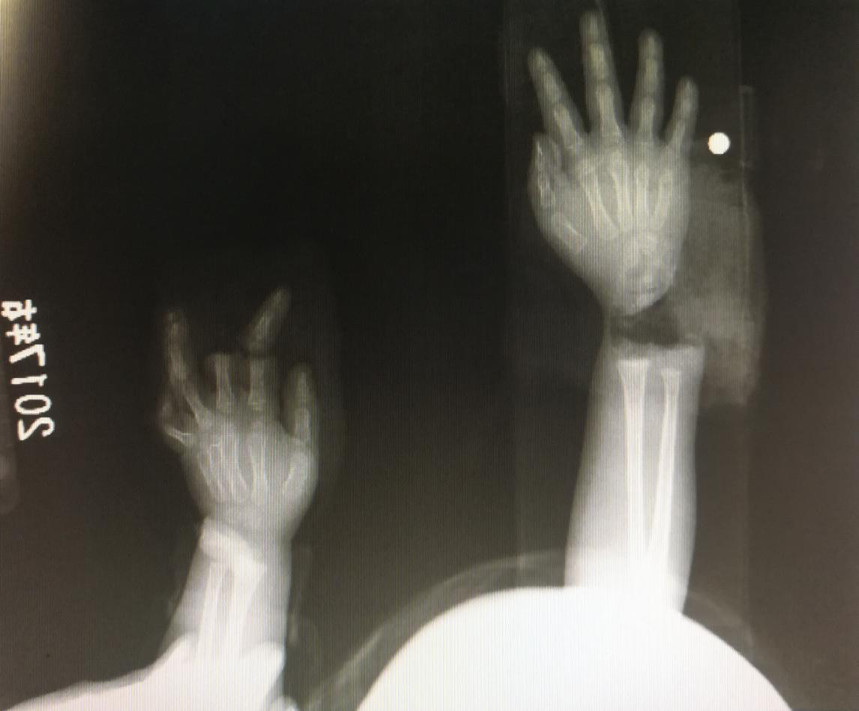

“急診在哪,急診在哪”,伴隨著一聲聲急促的問(wèn)詢(xún),一位年輕女士抱著渾身是血的小孩疾步前往急診室,懷里的小孩在疲憊與疼痛的交織下,時(shí)睡時(shí)醒。鑒于小孩的情況,急診醫(yī)生迅速安排給小孩拍了X光片,影像片結(jié)果顯示小孩左手手腕完全離斷,右手中、食指離斷,距離事發(fā)時(shí)間已經(jīng)3個(gè)多小時(shí),需盡快安排手術(shù)。

經(jīng)過(guò)長(zhǎng)達(dá)5個(gè)多小時(shí)的手術(shù),小宇(化名)終于被送出了手術(shù)室,離斷的手腕和手指均已完成再植,但關(guān)于斷指的存活與否還需要經(jīng)過(guò)一個(gè)十天的觀察期。小宇的主治醫(yī)生是長(zhǎng)沙年輪骨科醫(yī)院手足外科馬思成醫(yī)生,據(jù)馬醫(yī)生介紹,小宇受傷情況比較嚴(yán)重,失血過(guò)多,而且兩個(gè)手都存在完全離斷的情況,手術(shù)時(shí)安排了兩組醫(yī)生同時(shí)進(jìn)行,整個(gè)手術(shù)過(guò)程比較順利,目前小宇還處于觀察期。